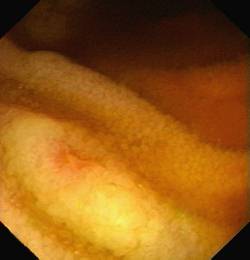

An immerse picture of small aphthous ulcer

Terminal ileum. Adjacent mucosa looks normal (including normal villi).